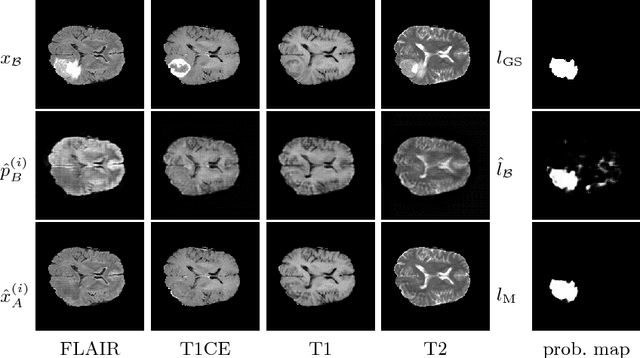

Abstract:We present a method to model pathologies in medical data, trained on data labelled on the image level as healthy or containing a visual defect. Our model not only allows us to create pixelwise semantic segmentations, it is also able to create inpaintings for the segmentations to render the pathological image healthy. Furthermore, we can draw new unseen pathology samples from this model based on the distribution in the data. We show quantitatively, that our method is able to segment pathologies with a surprising accuracy and show qualitative results of both the segmentations and inpaintings. A comparison with a supervised segmentation method indicates, that the accuracy of our proposed weakly-supervised segmentation is nevertheless quite close.